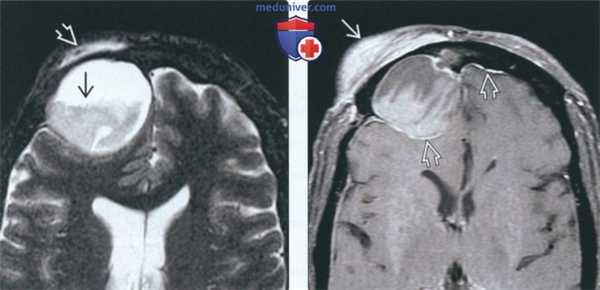

(Слева) При аксиальной МРТ Т2 FS визуализируется большое мукоцеле правой лобной пазухи с содержимым вариабельной интенсивности в нижних отделах. Мукоцеле распространяется в поверхностные мягкие ткани, приводя к их отеку.

(Справа) При аксиальной МРТ Т1 C+ FS у пациента с лобным мукоцеле: определяется отек и контрастное усиление поверхностных мягких тканей над разорвавшимся мукоцеле. Определяется также дуральное контрастирование передней черепной ямки, сопоставимое с ранним воспалением оболочек мозга.

(Слева) На аксиальной МРТ (Т2 ВИ FS) определяется большое мукоцеле правой лобной пазухи с уровнем «жидкость-жидкость» и компонентами с различной интенсивноаью сигнала. Мукоцеле распрсктраняется в поверхностные мягкие ткани, приводя к отеку.

(Справа) На аксиальной MPT (Т1 ВИ FS) у этого же пациента определяется отек и контрааное усиление поверхностных мягких тканей над разорвавшимся мукоцеле. Контрастирование твердой мозговой оболочки в передней черепной ямке сопоставимо с ранними воспалительными изменениями.